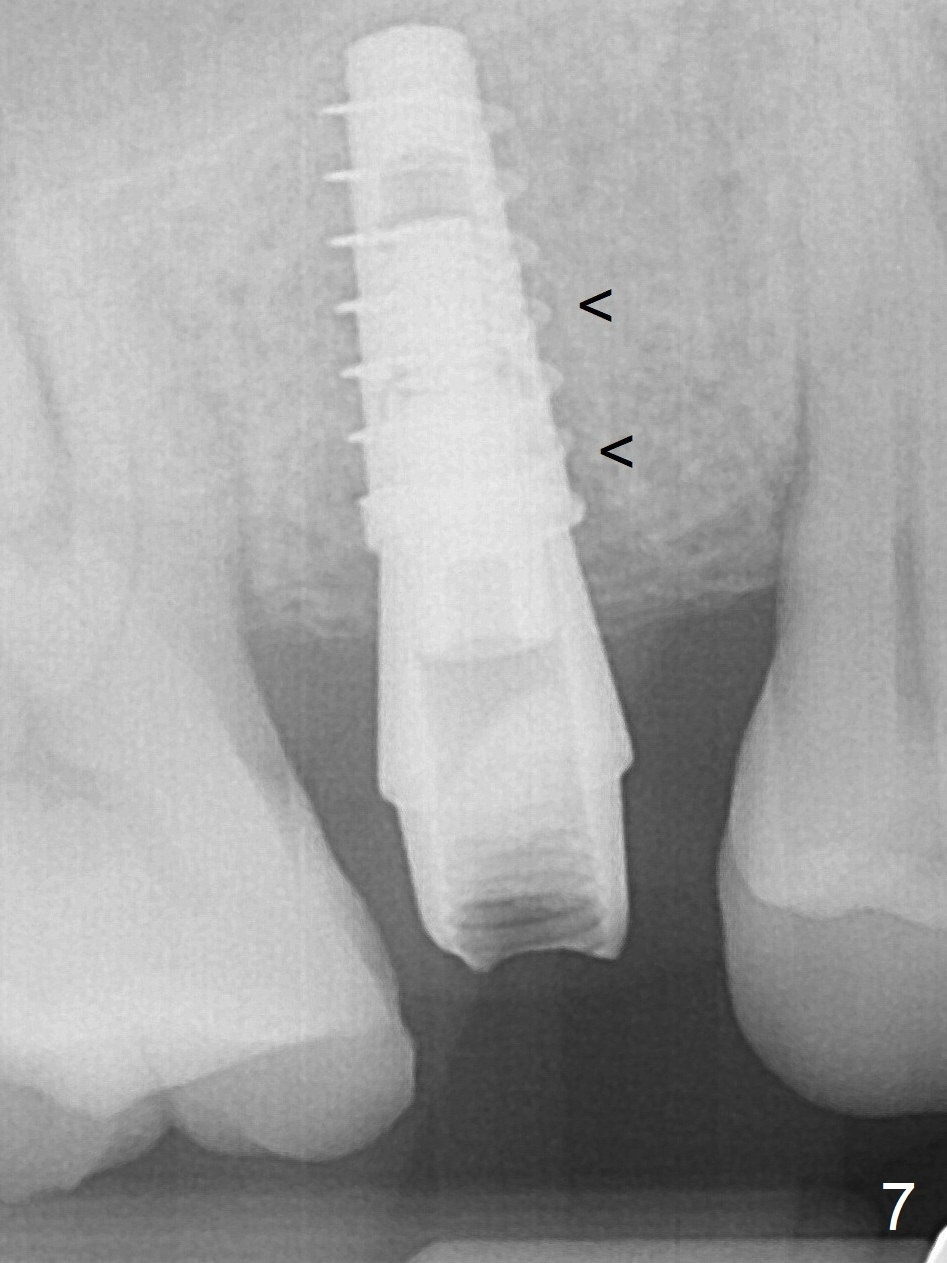

After extraction without drilling, a 4x11 mm dummy implant is placed as a tap drill with satisfactory stability (Fig.5). To get subcrestal placement, a shorter (4x9 mm) implant is inserted with insertion torque of >35 Ncm (Fig.6). In retrospect, a larger implant (4.5 mm) would be better in term of primary stability. After allograft placement into the buccal and lingual gaps, a 4.5x4(4) mm abutment is placed for an immediate provisional. The sinus floor is penetrated by the implants without bone graft for sinus lift. There is a peri-implant gap 7 months postop (Fig.7<) . When the loose abutment is being retightened, the patient feels pain, although the gingiva appears healthy (Fig.8). A larger implant should have been used; the abutment should have been removed.